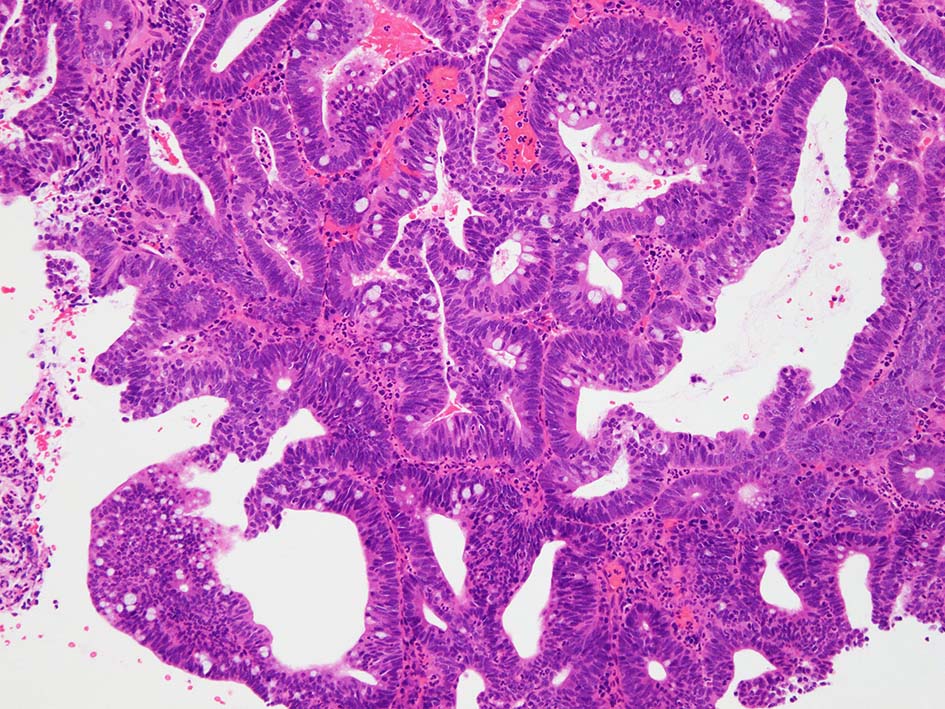

腸管型の腺癌。大腸の高分化腺癌と組織学的に区別は難しい.

neutrophilic exudate の付着する腸管型腺癌部分. 核はより腫大し円形、vesicularとなっている. 上記腸管型とはCK20, CK7のそまりが異なっていた. 変性のためかもしれない.